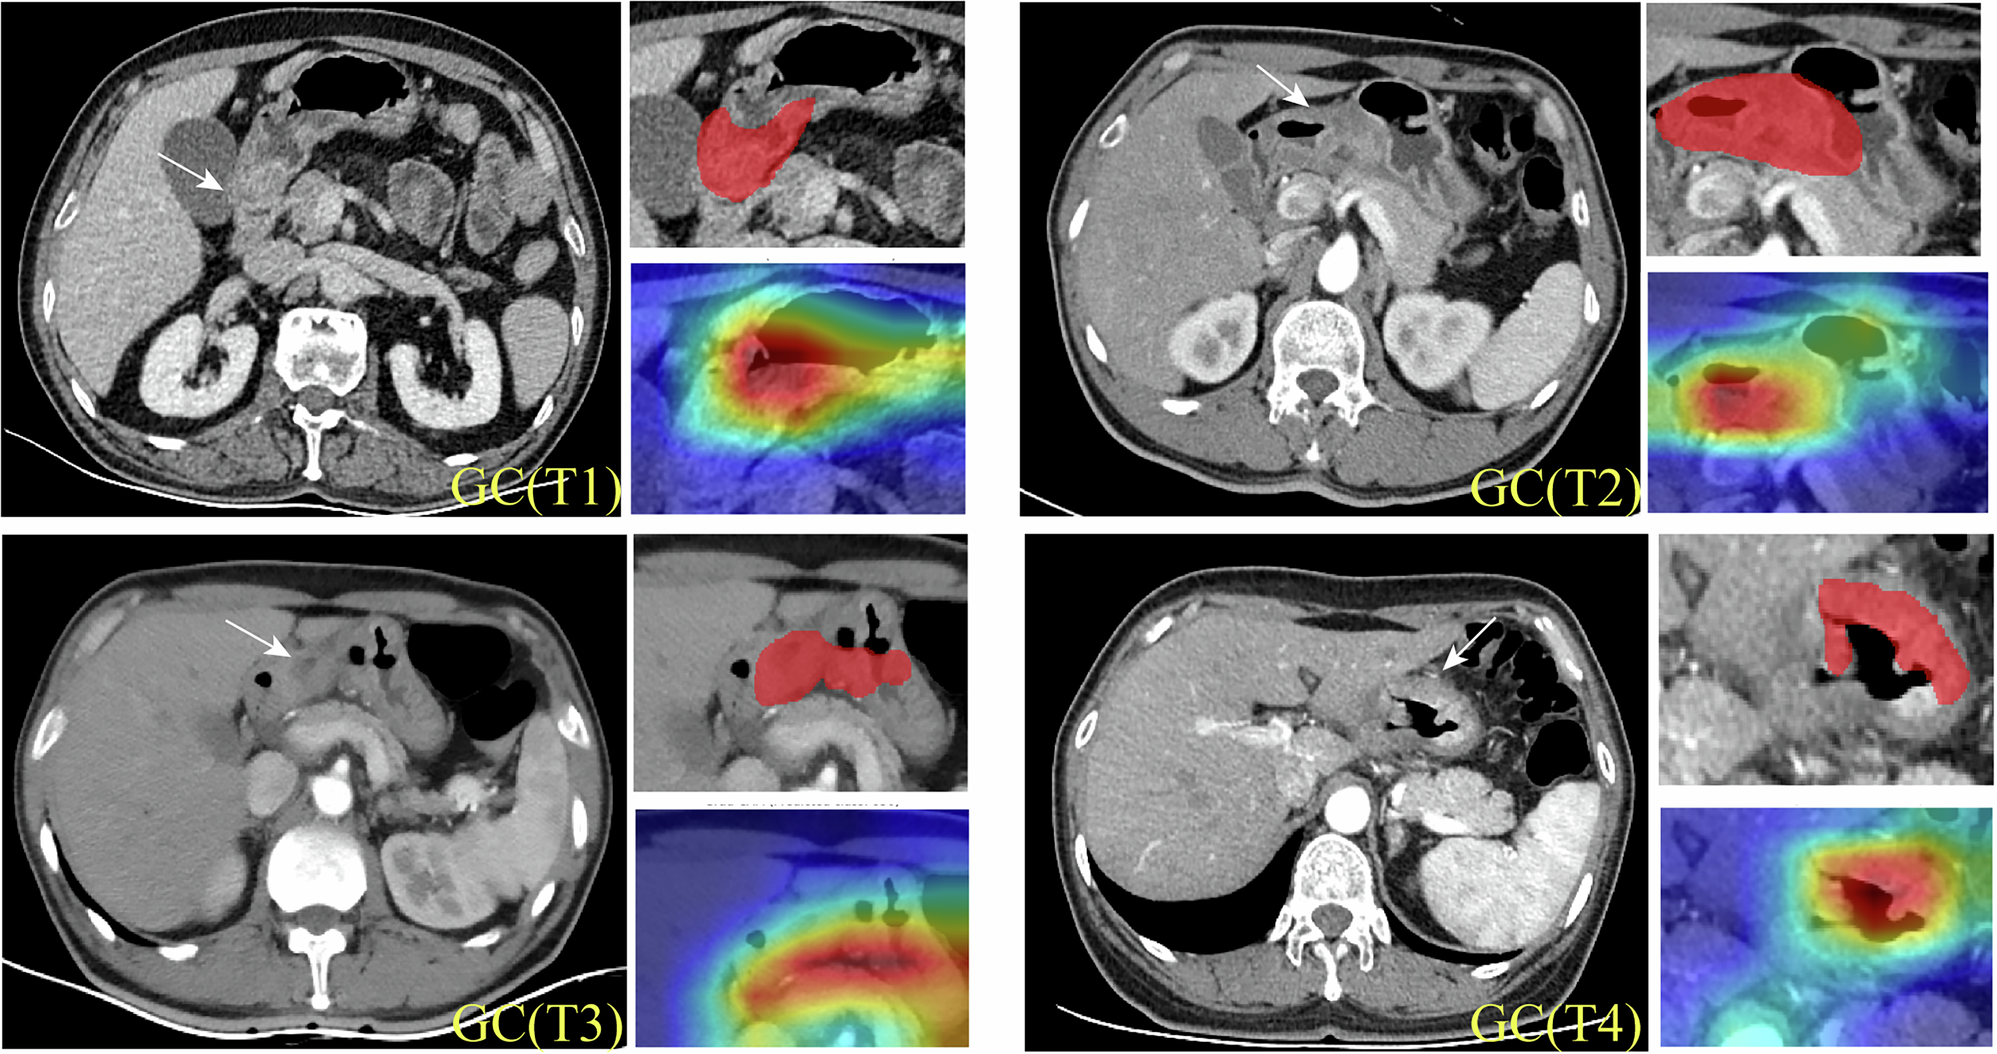

Fig. 3: Grad-CAM visualization.

For representative T1–T4 cases, portal-venous CT images (left) and color heatmaps (right) highlight mucosa (cT1), muscularis propria (cT2), serosal surface (cT3), and pancreatic invasion (cT4).